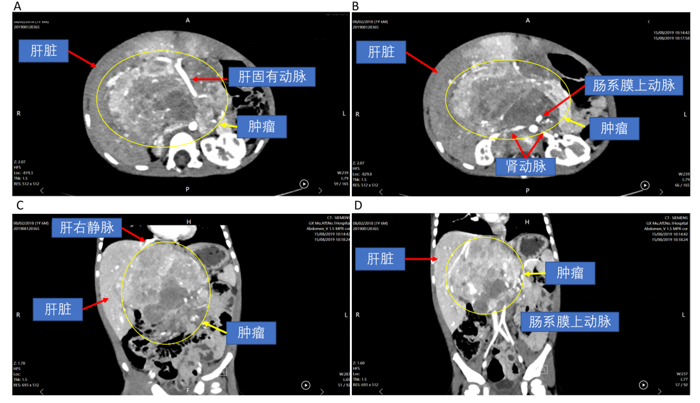

▲文文腹部巨大、复杂神经母细胞瘤CT。

▲李大爷CT显示,肿瘤位于肝脏所有大血管围成的“危险三角区域”。

2023年,56岁的李大爷(化名)因肝纤维化合并肝癌入院。肿瘤侵犯“第二肝门”,即肝脏血液回流进入心脏的核心危险区域,常规切除会导致肿瘤残留和残余肝脏体积不足;而异体肝移植则面临费用高昂、供体匹配困难、免疫排斥等问题。